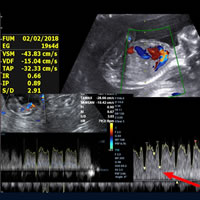

Curso de Ecodoppler en Obstetricia y Ginecología 2026

Curso de Ecocardiografía y Cardiología Fetal 2026